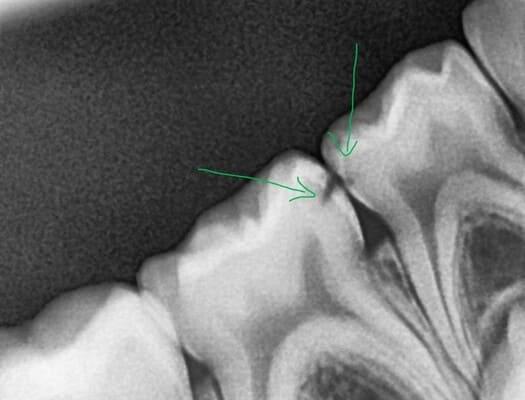

Не завжди маленька дірочка це про маленький карієс. Фісурний карієс досить часто розвивається вглиб і здатен вражати ще не достатньо мінералізовані зубні тканин юних пацієнтів. Зазвичай страждає жувальна поверхня, але інколи вражається і бічна поверхня, що має таку анатомічну структуру, як сліпа ямка. Даний пацієнт прийшов до нас саме з такою проблемою. Але завдяки своєчасному зверненню і гарній роботі нашої команди, ми змогли зупинити каріозний процес та відновити анатомію жувальної поверхні.

У нашій клініці ми дбаємо не лише про здоров’я тимчасових зубів у малечі, а й активно займаємося лікуванням постійних зубів у підлітків — адже саме в цей період формується основа для майбутньої здорової усмішки. До нас звернувся юний пацієнт зі скаргами на застрягання їжі між нижніми жувальними зубами, що викликало дискомфорт під час прийому їжі. Після проведення рентгенологічного обстеження було виявлено контактний карієс, а також застарілу реставрацію на одному із зубів. Було проведено лікування карієсу та оновлення реставрації з урахуванням анатомії зубів. Усе відбулося комфортно для пацієнта — під місцевою анестезією та в спокійній атмосфері. У результаті відновлено правильний контакт між зубами, що повністю усунуло проблему та повернуло комфорт під час їжі.